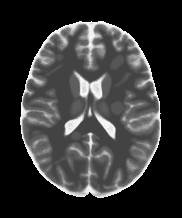

Figure 2: Example axial slice from the clinical brain dMRI, involving b-values of 0, 300 and 1000 s/mm2.

Three orthogonal (x, y, z) diffusion directions were sampled at b-values of 0, 300 and 1000 s/mm2. The images have spatial resolution of 1.4×\times×1.4×\times×5 mm3. For the sake of denoising quality evaluation, the number of scan repetitions was set to the maximum possible value of 32. The images were exported as raw data and reconstructed using the algorithm described in [10, Section 3.1]. An example slice at all b-values is shown in Figure 2.